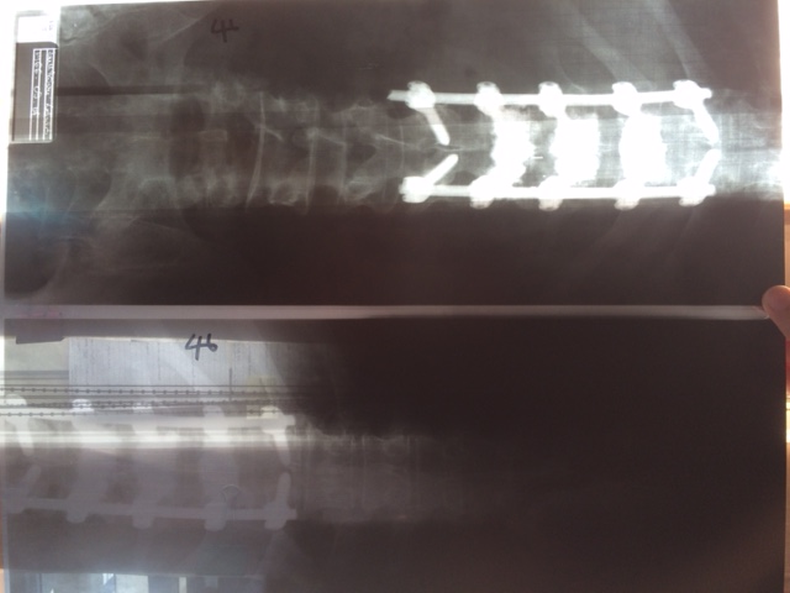

A legutóbbi operáció során (összesen már 19 órát töltött kés alatt…) két fémlemezt tettek a gerincébe, amelyet tíz titáncsavar rögzít, s a doktorok a szeptember 9-ei felülvizsgálaton döntik majd el, folytathatja-e a versenyzői pályafutását, és ha igen, mikor ülhet újra terepraliautóba.

„Öt hete volt a műtét, azóta folyamatosan járok vízi edzésekre, és egyre jobban érzem magam, kivéve azt a huszonöt centis vágást, ami a hátamon van, mert az még húzódik. Ja, és kicsit furcsa érzés, amikor hanyatt fekszem, olyan, mintha folyamatosan feküdnék valamin, csakhogy az a valami a testemen belül van – mondta Bunkoczi, aki azt is elárulta, a második műtétre azért volt szükség, mert folyamatosan fájt a dereka, és így stabilizálták tovább a már megműtött gerincét. – Összesen tizenkilenc órán keresztül műtötték a gerincemet, úgyhogy most már csak jó lesz! Én úgy készülök, hogy jó lesz, és akkor januárban újra autóba ülhetek. Öt hónapom van addig, ami ha akarom sok, ha akarom kevés, de minden nap teszek valamit azért, hogy vissza tudjak térni a versenyzéshez, mert ez mindennél jobban motivál.”